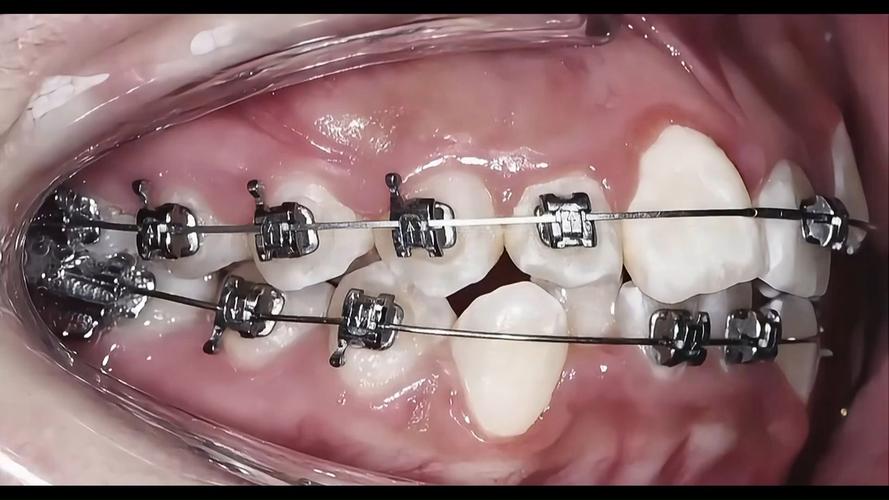

矫正牙齿(正畸)治疗中,部分患者可能需要结合手术实现更理想的矫治效果,例如正畸种植钉辅助内收、骨皮质切开术加速牙齿移动、正颌手术矫正严重颌骨畸形等,随着医疗可视化技术的普及,矫正牙齿手术视频逐渐成为患者了解术式、医生学习交流的重要载体,这类视频通过直观展示手术操作流程、器械使用细节及术后效果,帮助患者消除信息差,也为规范化诊疗提供了参考,但观看手术视频时需保持理性,结合专业指导才能正确理解其价值与局限。

不同矫正手术的操作难度、适应症和视频关注点存在差异,以下是几种常见术式的核心内容,可通过视频直观学习:

| 正畸种植钉植入术 | 牙齿内收需要强支抗、压低伸长牙、纠正颌骨旋转等 | 局部麻醉→定位植入点(避开牙根、神经)→植入种植钉→术后拍片确认位置→术后护理指导 | 植入角度需与牙根平行,避免损伤牙根;术后保持口腔卫生,防止种植钉周围炎 |